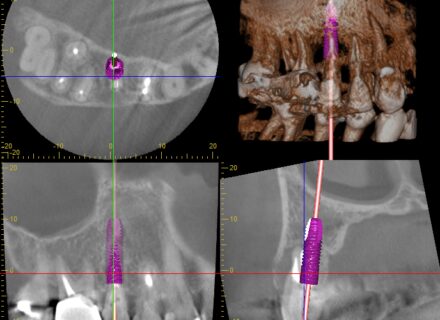

8年経過したインプラント症例:前歯の違和感を訴える40代女性患者 はじめに インプラント治療後の長期経過観察は、治療の成功を評価する上で非常に重要です。今回、8年前にインプラント治療を行った40代…